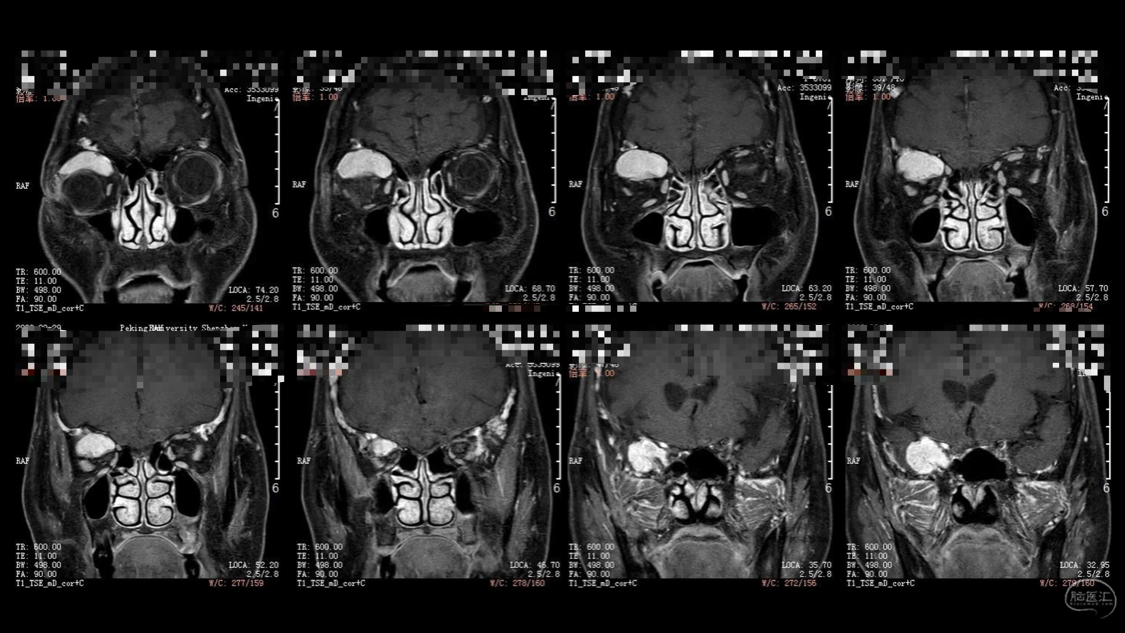

陈保东教授手术作品-右眶内及海绵窦旁孤立性纤维瘤